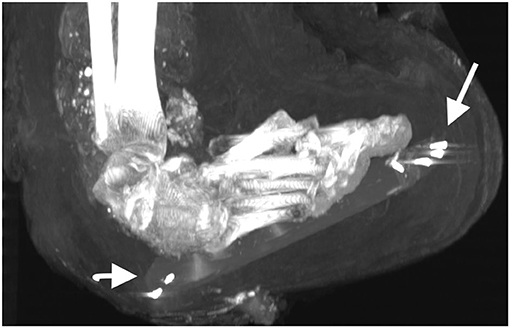

Estimaciones anteriores en cuanto a la edad de Amenhotep I basadas en exámenes de rayos X, primero en 1932, encontraron que tenía entre 40 y 50 años, y luego, a partir del análisis de los dientes en 1967, ubicaron su edad en 25. Sin embargo, las tomografías computarizadas recientes parecían en la sínfisis del pubis (un hueso en la parte inferior de la pelvis que se alisa con la edad) y colocó la edad de su muerte en 35 años.

También se encontraron treinta amuletos/piezas de joyería. Amuletos de metal, cuarzo, piedra y arcilla cocida de varias formas y diseños fueron envueltos con la momia en diferentes lugares, con uno sobre el corazón y dos colocados dentro de la cavidad anormal. Los embalsamadores habrían pronunciado hechizos y envuelto estos como protección para el difunto. Otros artículos incluyen un cinturón de 34 cuentas de oro colocadas en la parte inferior de la espalda de la momia, alfileres de hueso o marfil y clavos metálicos que se usan para sujetar envolturas y extremidades en posición.